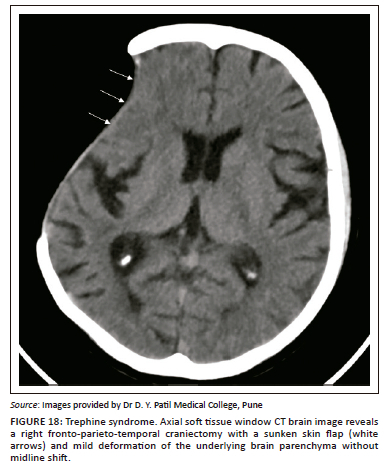

Sinking skin flap syndrome

Sinking skin flap syndrome, or Trephine syndrome, is an intermediate to late post-operative complication in patients who undergo craniectomy. There is a sunken appearance of the skin flap and concave appearance of the underlying parenchyma due to chronic exposure of the brain to atmospheric pressure causing deformity of the underlying parenchyma (Figure 18).21 Unlike paradoxical herniation, there is no midline shift, subfalcine or uncal herniation. The patients usually present with vague complaints such as headache, dizziness, mood changes and fatiguability.21